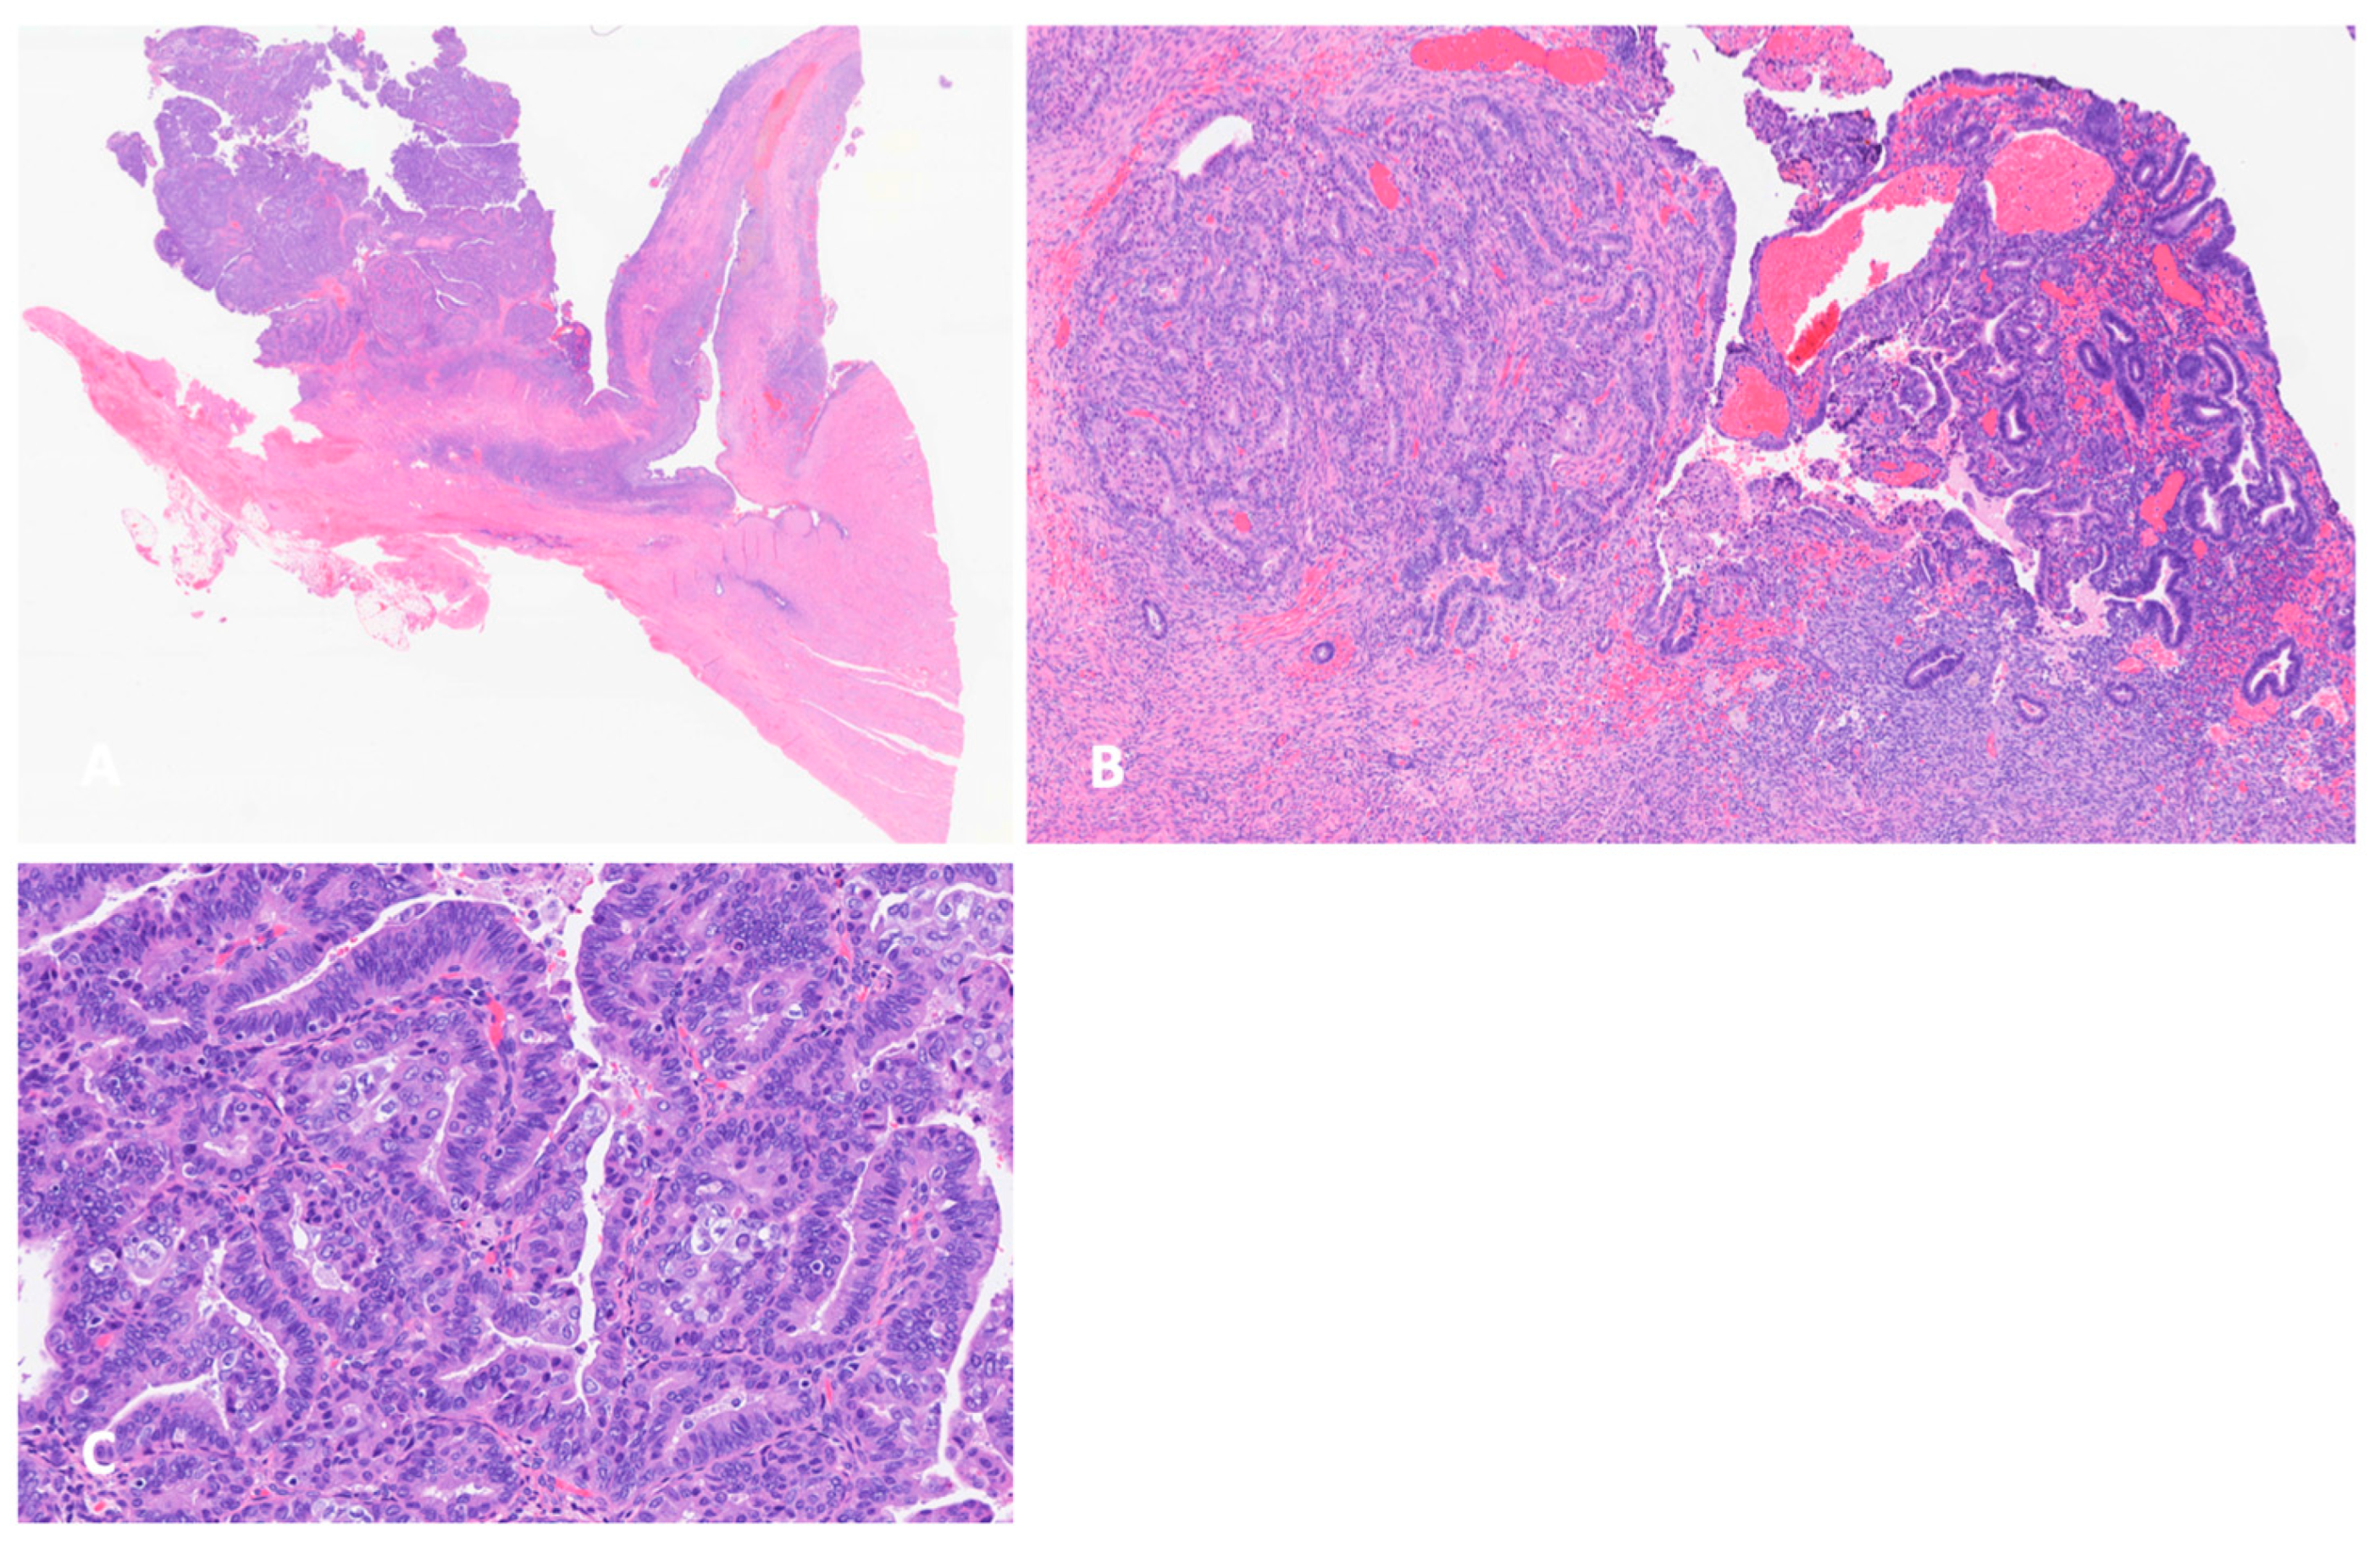

3.2. Histology and Pathogenesis of Endometriosis-Associated Ovarian Cancer

- Czernobilsky, B.; Morris, W.J. A histologic study of ovarian endometriosis with emphasis on hyperplastic and atypical changes. Obstet. Gynecol. 1979, 53, 318–323. [Google Scholar] [PubMed]

- LaGrenade, A.; Silverberg, S.G. Ovarian tumors associated with atypical endometriosis. Hum. Pathol. 1988, 19, 1080–1084. [Google Scholar] [CrossRef] [PubMed]

- Fukunaga, M.; Nomura, K.; Ishikawa, E.; Ushigome, S. Ovarian atypical endometriosis: Its close association with malignant epithelial tumours. Histopathology 1997, 30, 249–255. [Google Scholar] [CrossRef] [PubMed]

- Tanase, Y.; Furukawa, N.; Kobayashi, H.; Matsumoto, T. Malignant Transformation from Endometriosis to Atypical Endometriosis and Finally to Endometrioid Adenocarcinoma within 10 Years. Case Rep. Oncol. 2013, 6, 480–484. [Google Scholar] [CrossRef] [PubMed]

- Wepy, C.; Nucci, M.R.; Parra-Herran, C. Atypical Endometriosis: Comprehensive Characterization of Clinicopathologic, Immunohistochemical, and Molecular Features. Int. J. Gynecol. Pathol. 2024, 43, 70–77. [Google Scholar] [CrossRef]